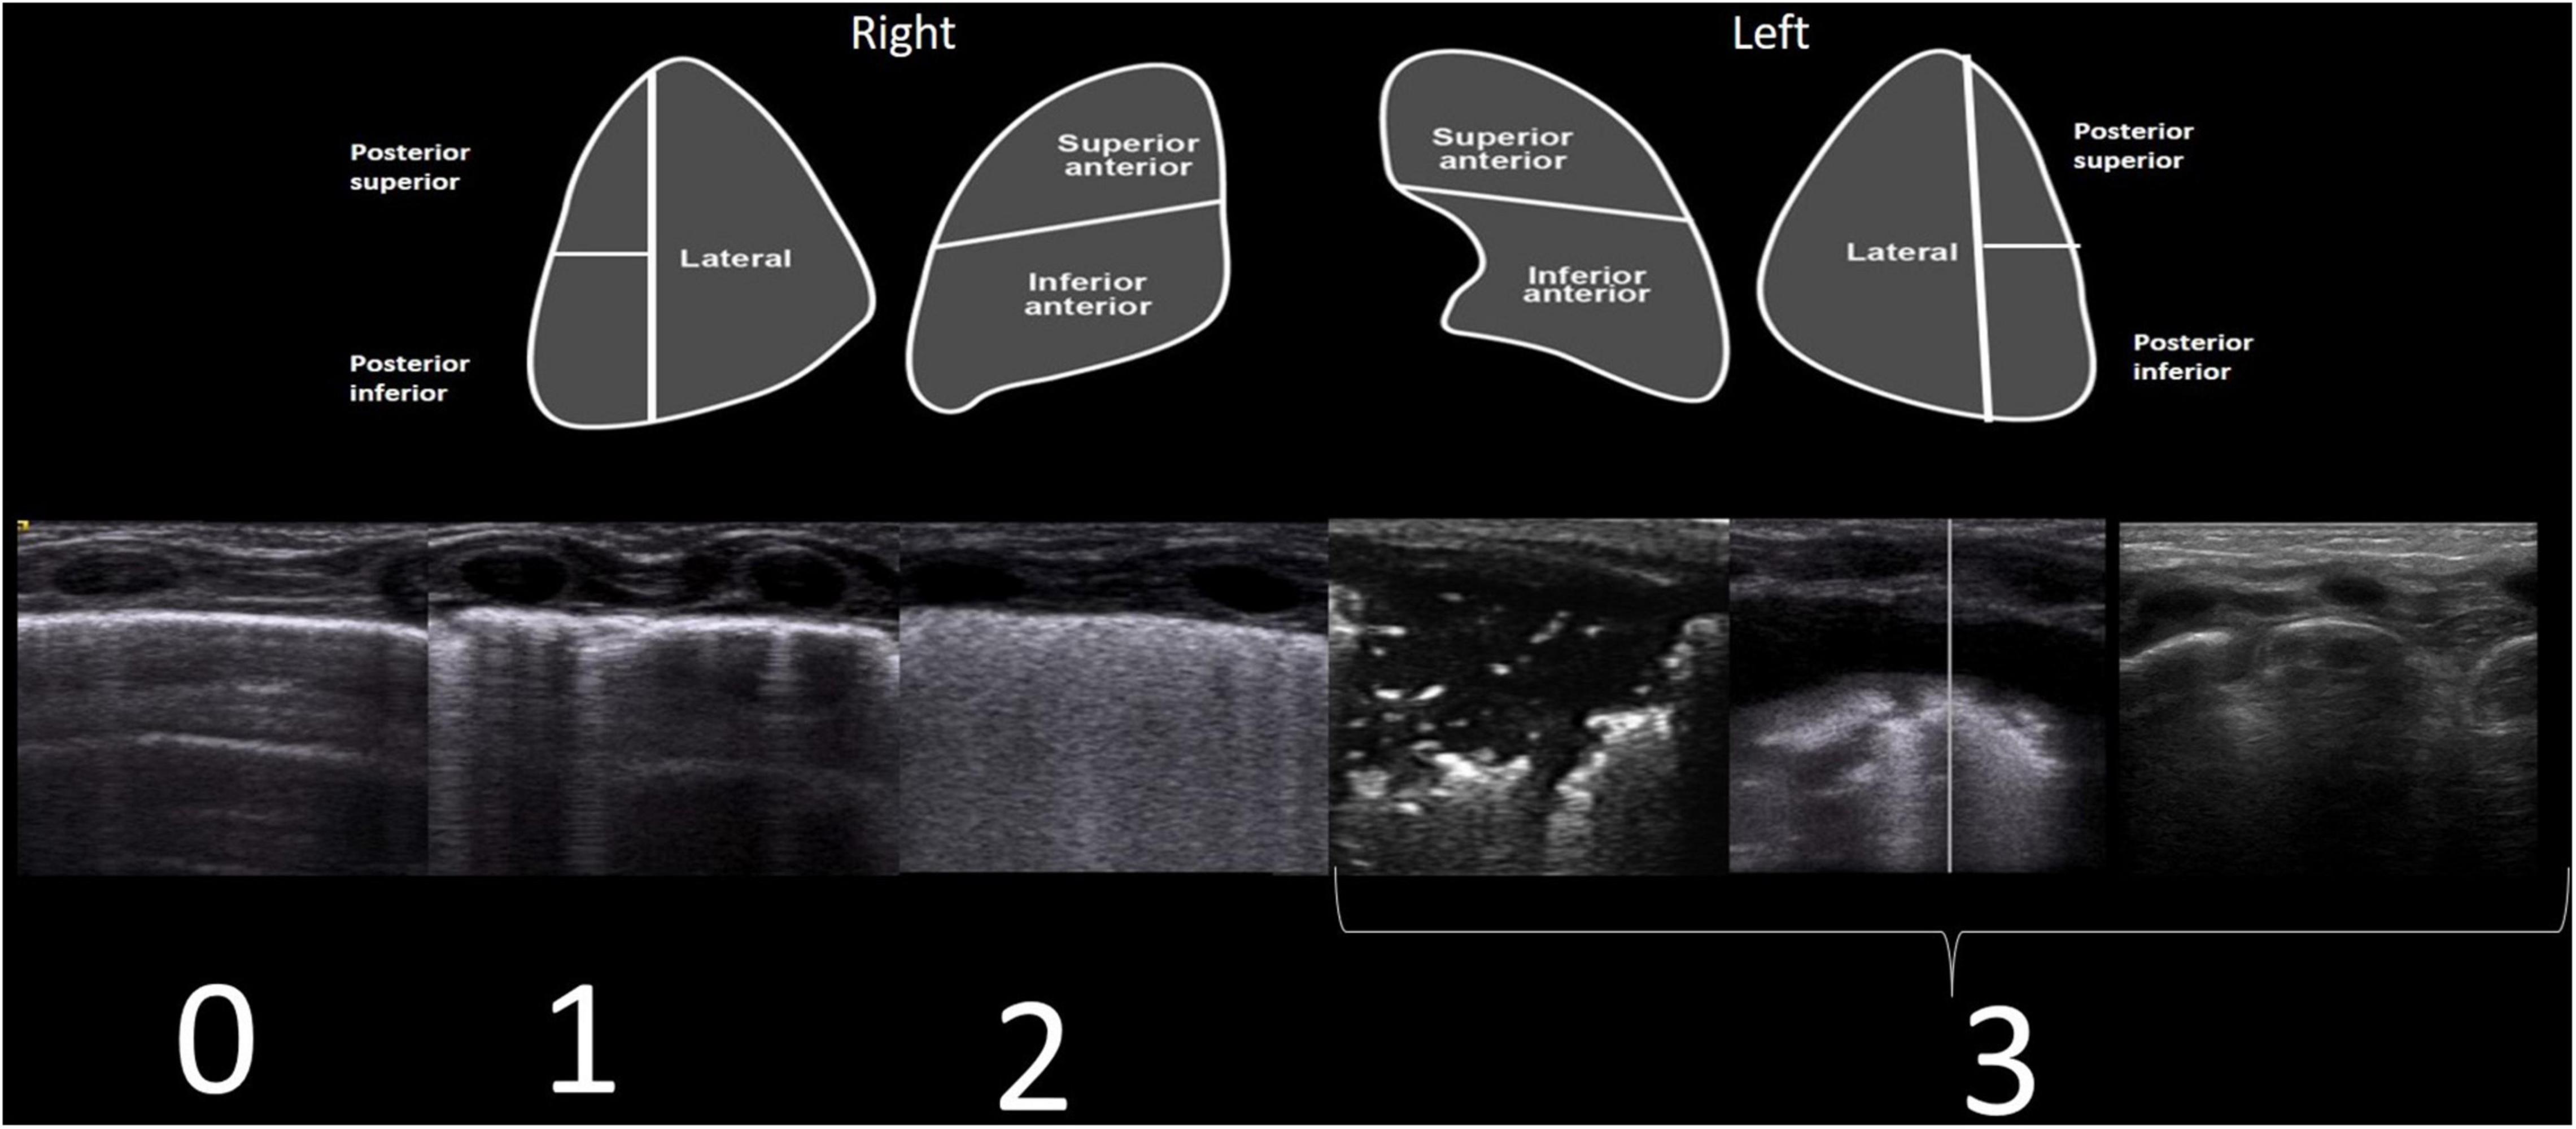

Ten regions were explored (anterior superior and inferior, lateral, and posterior superior and inferior, right and left). A semi-quantitative LUSS was calculated through both transverse and longitudinal scans, with the following scores: 0 (defined by the presence of A-lines and pleural sliding); 1 (defined as the presence of three or more well-spaced B-lines); 2 (defined as the presence of coalescent B-lines giving a white lung appearance); and 3 (defined as the presence of extended consolidations and pleural effusion or absence of the lung in the case of lung malformations) (Figure 1).

Figure 1. Each lung was divided into five areas (upper part of the figure). For each area, a score of 0–3 was established. LUSS corresponds to four different patterns (lower part of the figure). Scores were given as follows: 0 (defined by the presence of A-lines and pleural sliding); 1 (defined as the presence of three or more well-spaced B-lines); 2 (defined as the presence of coalescent B-lines or white lung); and 3 (defined as the presence of extended consolidations and pleural effusion or absence of lung in the case of lung malformations).